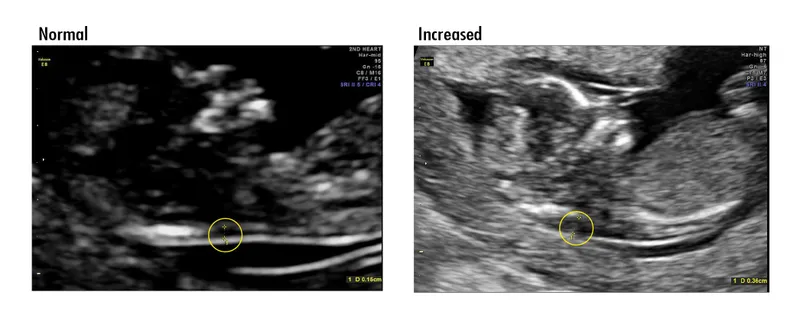

- Ultrasound: Nuchal Translucency (NT). A fluid collection >3.0 mm is a key marker.

- ↑ Nuchal Translucency/Fold: Strongest marker for Trisomy 21. NT >3 mm in 1st trimester.

⭐ While most soft markers are non-specific, a thickened nuchal fold (≥6 mm) in the second trimester is one of the strongest individual markers for Down syndrome.

- Increased nuchal translucency (NT) is a key first-trimester marker for aneuploidies like Trisomy 21.